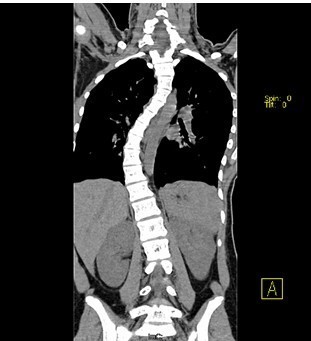

患者女,13岁,因“发现脊柱侧凸畸形4月”入院。患者4月前家长无意间发现胸背部脊柱侧凸,双肩不等高,无牛奶咖啡斑、无皮下结节,不伴活动耐力下降、气促、心悸、胸背痛、腰痛,日常活动及运动能力正常,在当地医院检查后建议手术治疗,到我院就诊,门诊以"特发性脊柱侧凸"收入住院。

查体:胸段脊柱向右侧凸,右侧胸廓后部凸起,剃刀背畸形,剃刀背高度2cm,右肩高,骨盆略向右倾斜,四肢及关节未见异常,未查见牛奶咖啡斑。脊柱各棘突及棘突旁无压痛及扣痛。胸腰部前屈、后伸及侧屈、侧旋范围正常,双下肢等长,未发现感觉减退区,四肢肌力5级,生理反射均正常引出,病理反射未引出。 辅查:X片示胸段脊柱以胸8为中心明显右侧弯畸形,胸段上段及腰段相应轻度左突侧弯。

初步诊断:特发性脊柱侧凸(Lenke:ⅡA ̄型) 诊疗计划: 拟经后路脊柱侧凸矫形+同种异体骨植骨+椎弓根螺钉内固定术术